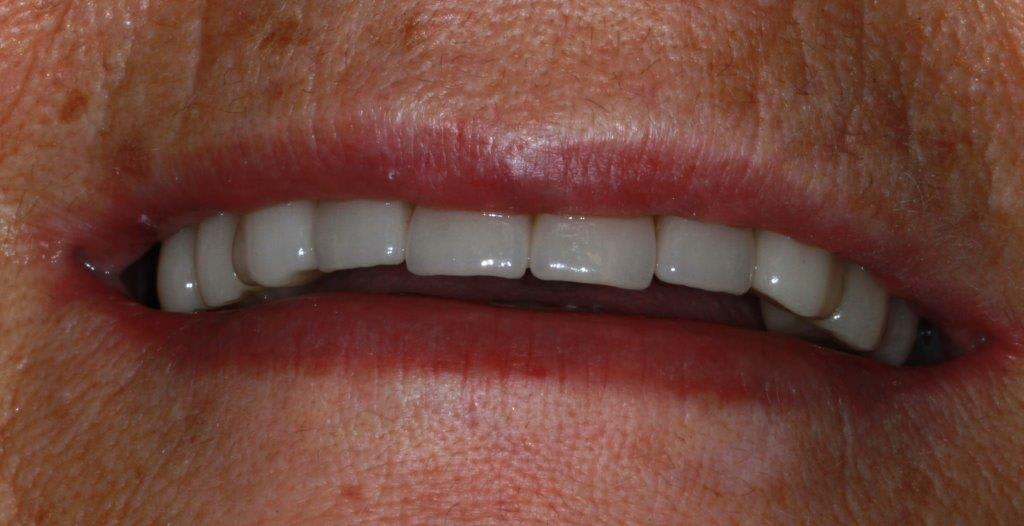

des nouvelles de ce cas... mise en charge des implants et attelle incisive mandibulaires avec suppression du diastème

expansion qui donne un résultat correcte je crois

la temporisation ce fut avec sont stellitte (retouché) puis des provisoires résine, je n'ai pas voulu faire l'empreint des ceram du haut en même temps que les implants.